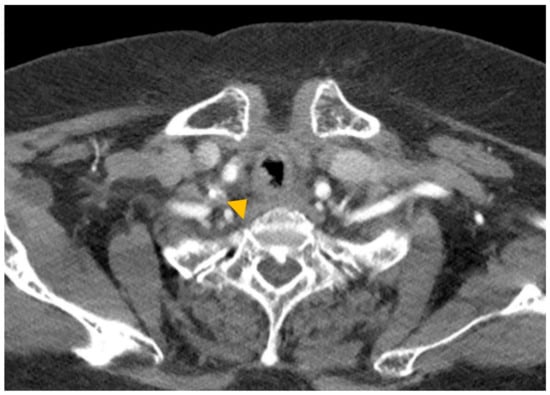

A 74-year-old woman was admitted to our hospital with dyspnea and chest pain. She had hypertension, type 2 diabetes mellitus, heart failure, persistent atrial fibrillation, and chronic obstructive pulmonary disease (COPD). The patient did not use an inhalant for COPD because of low adherence to inhalation therapy. Human immunodeficiency virus testing was negative. On the second day of admission, she complained of chest pain and showed a decrease in consciousness. Torsade de pointes and ventricular fibrillation were observed. She underwent intensive care unit (ICU) treatment for 10 days, including mechanical ventilation, direct-current cardioversion, and a temporary pacemaker. The patient received prednisolone from 5 mg to 10 mg per day with inhaled budesonide/salbutamol/ipratropium for two months from the day of ICU admission to treat the COPD exacerbation and control dyspnea. After being transferred to the general ward, the patient remained stable with tapering and discontinuation of steroid administration. The patient developed throat discomfort on the 68th day of hospitalization. Since then, her dyspnea gradually worsened without desaturation and CO2 retention. On the 76th day of hospitalization, the patient complained of sustained throat discomfort and dyspnea with stridor. Neck computed tomography revealed a narrowing of the proximal trachea with a diffuse wall thickening and intraluminal irregularity (Figure 1), and video laryngoscopy detected a tracheal mass-like lesion. On the same date, acute respiratory failure occurred (the oxygen saturation by pulse oximeter was 56%, and the respiratory rate was 32 breaths per min). CO2 retention was detected in the arterial blood gas analysis (pH: 7.037, PaCO2: 66.1 mmHg, PaO2: 205.3 mmHg) at 15 L/min via reservoir bag. The patient was transferred to the ICU for mechanical ventilation. There was no evidence of nosocomial pneumonia in the chest X-ray, and serum C-reactive protein was normal (<0.5 mg/dL). No severe obstructive respiratory pattern was observed on the flow graph of the ventilator monitoring, and the CO2 retention immediately improved after endotracheal intubation in low grade pressure support. On the second day after intubation, chest computed tomography showed an aggravation of the multifocal diffuse tracheal wall thickening with luminal narrowing (Figure 2A) and a new-onset peribronchial ill-defined consolidation in the right upper lobe (Figure 2B). The piperacillin-tazobactam was initially administered for treatment of pneumonia. Bronchoscopy revealed a proximal tracheal narrowing with multiple ulcerations of the tracheal mucosa surrounded by an erythematous margin (Figure 3A). Multiple biopsies were performed at the base and margin of the ulceration (Figure 3B). Microscopically, reactive squamous atypia was observed in the background of the ulcer and granulation tissue (Figure 4A). In the squamous epithelium, numerous keratinocytes with virus-infected changes, including ground glass nuclei and nuclear molding, and multinucleated giant cells were observed (Figure 4B). Immunohistochemistry showed positive results for the anti-HSV antibody. A few viral cytopathic cells were noted in the granulation tissue, which were positive for the anti-CMV antibody (Figure 4C). The CMV real-time polymerase chain reaction (PCR) in the bronchial alveolar lavage fluid was also positive (31,775 copies/mL). Therefore, intravenous ganciclovir (300 mg twice daily), which is effective against HSV and CMV, was administered for 44 days. Despite the cessation of the sedative drugs, the patient’s consciousness did not improve. Brain magnetic resonance imaging revealed a multifocal petechial hemorrhage in the bilateral temporo-parietal lobe and left insula and minimal subdural hygroma along the left cerebral convexity. These findings were consistent with hemorrhagic encephalitis. The cerebrospinal fluid examination was within normal limits (white blood cells, 1 cells/µL; protein, 43 mg/dL). The viral PCR results for enterovirus, CMV, HSV, and varicella-zoster virus were all negative. On the 19th day after intubation, a percutaneous dilatational tracheostomy was performed for the tracheal stricture. The patient was transferred to the general ward on the 29th day after ICU readmission. A follow-up bronchoscopy was performed about every two weeks. On the 44th day of ganciclovir therapy, the follow-up bronchoscopy showed an improvement in the ulceration with scars (Figure 5). Microscopically, no lesions were suspected from viral infection.

Figure 1. Neck computed tomography image. A diffuse wall thickening and intraluminal irregularity are noted in the proximal trachea (arrowhead).